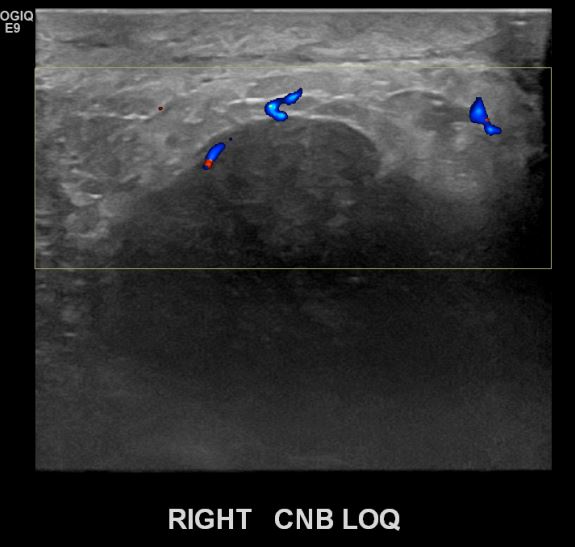

상기환자 우측유방에 딱딱한 멍울이만져져 내원하신 30대여성분으로 좌측유방의 혹 조직검사시행후 유방암 진단되었습니다